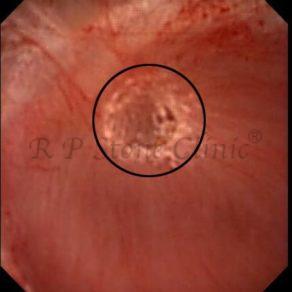

The Below Images Show Small Stones attached to the Renal Papillae.

These images are taken as snap shots from the video recording of RIRS Surgery done at our hospital. These are Randall’s Plaques seen with Digital FLEX XC & Digital FLEX XC S. The cream or whitish patches are seen on the tips of RENAL PAPILLAE as seen in images below.